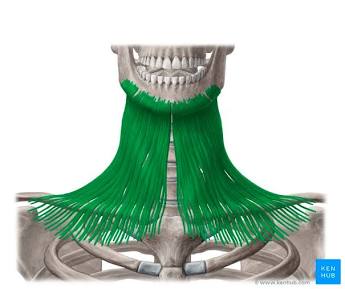

Platys

Flat.